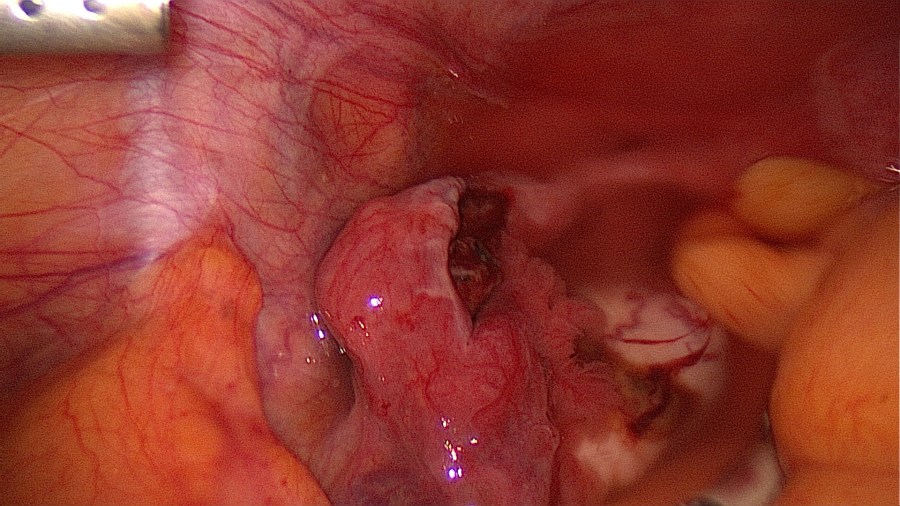

Visualize the ectopic pregnancy.

Linear salpingotomy: open the tube directly over the tubal pregnancy with a straight incision made with a monopolar needle (Taran, F-A et al., 2015).